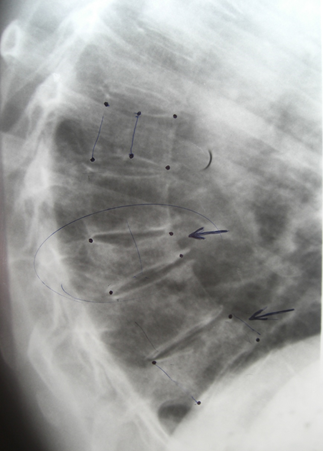

Figure 3 Lumbar vertebral fractures, the number 0 is normal, 1,2 and 3 show different VF (Genant Classification).

Different methods were described to evaluate VF, already in 1947 Fletcher proposed a “wedging index” to describe the variations of anterior vertebral heights and in 1960 Barnet and Nordin described the “biconcavity index” as the ratio of the average vertebral height and the anterior height calculated in a lumbar vertebra and its value of 0.8 was indicative of osteoporosis, but has fallen into disuse since it correlated poorly with Densitometry. Detailed descriptions of the measurements of vertebral heights are due to Hurxthal in 1968 to evaluate coinages. Other semiquantitative methods were described: Smith's method, Meunier's method classifying into grades 1,2 and 3 (normal vertebra, biconcave and collapsed) and even calculated the RVI (radiological vertebral index); the Kleerekoper method modified the IRV and introduced SDV (vertebral deformity score) based on the type of deformity and finally Henry K. Genant3 developed his method of evaluating VF by visual inspection and the degree of reduction of vertebral heights , differentiate deformities because a deformity is not always a fracture but a VF is always a vertebral deformity. Figure 8. differentiate deformities because a deformity is not always a fracture but a VF is always a vertebral deformity. Figure 8. differentiate deformities because a deformity is not always a fracture but a VF is always a vertebral deformity. Figure 8.

Grade 1 has a previous height reduction of 20 to 25% and an area reduction of 10 to 20%, moderate (grade 2) of 25 to 40% and area reduction of 20 to 40%, severe (grade 2). grade 3) of more than 40% at any height and area. This method has been evaluated and tested in different epidemiological studies and clinical studies with drugs. In Figure 3 the number 0 is normal, 1 corresponds to grade 1, mild; the number 2 to a grade 2 and 3 to a severe Genant grade 3, is calculated from the “vertebral deformity index” P: length of the posterior wall, A: length of the anterior wall, therefore: PA/P x 100 = % that P is less than A. With this method, the IFC (spinal fracture index) can also be calculated by adding all the grades assigned to the vertebrae and dividing by the number of vertebrae.